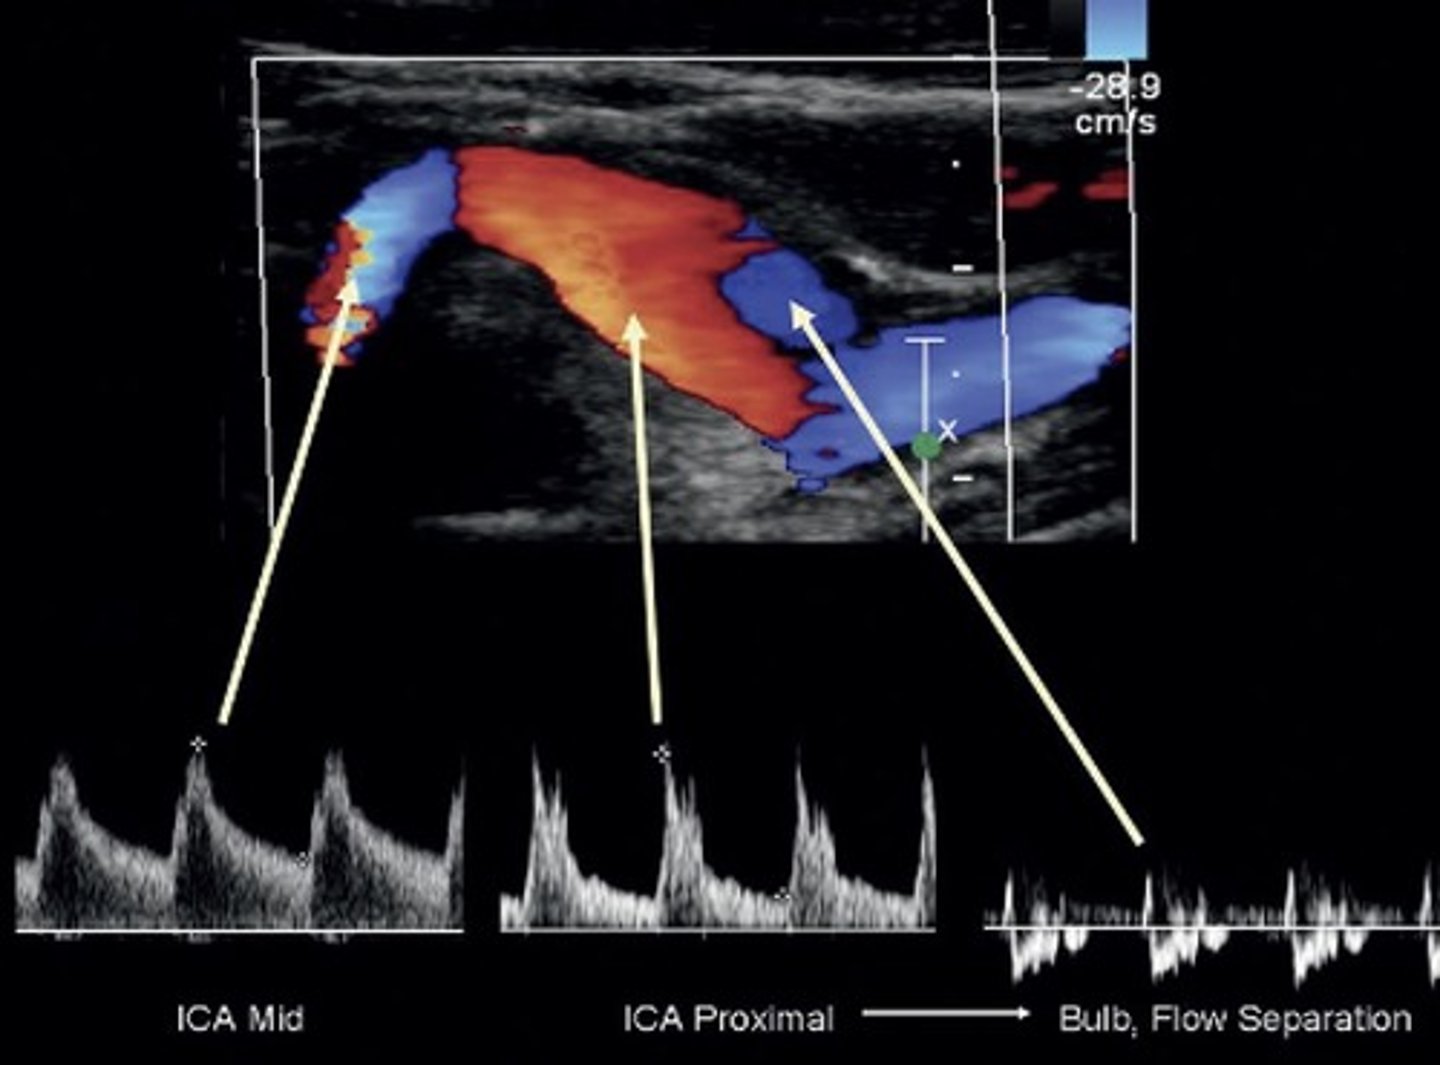

Carotid Bulb

Normal to have turbulent flow at separation/divider

Prox ICA - just after bulb

Mid ICA

Normal ICA Waveform

Lowest resistance